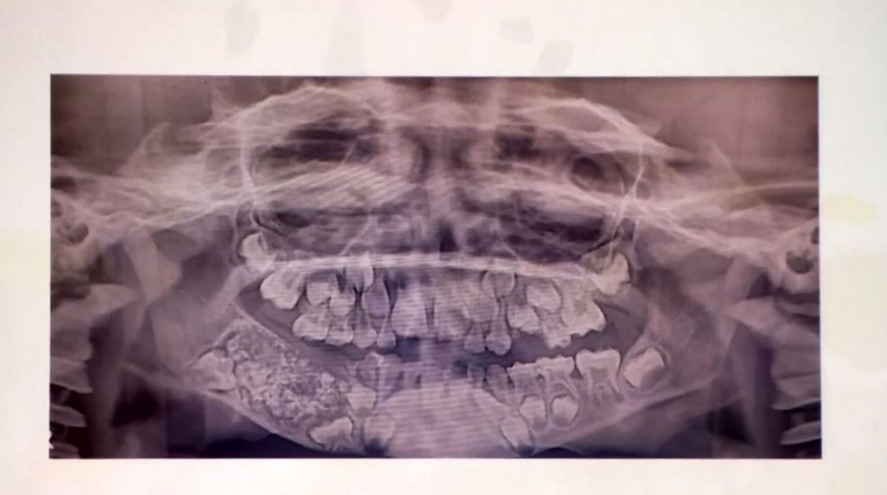

Les médecins ont très vite effectué un examen, avec une radiographie à l’appui. Une lésion assez importante a été détectée, où se trouvait aussi une sorte de petit sac qui contenait des centaines de petites dents. Une intervention chirurgicale a été faite dans l’urgence pour retirer cette petite poche. Le garçon a subi une opération qui a duré cinq longues heures. Dans le sac, les médecins ont retiré en tout 526 dents, une première dans le monde. D’après eux, Ravindran en a souffert depuis quatre ans déjà. Une enflure a été déjà remarquée par les parents lorsque l’enfant était âgé de 3 ans, mais ils ne se sont pas inquiétés.